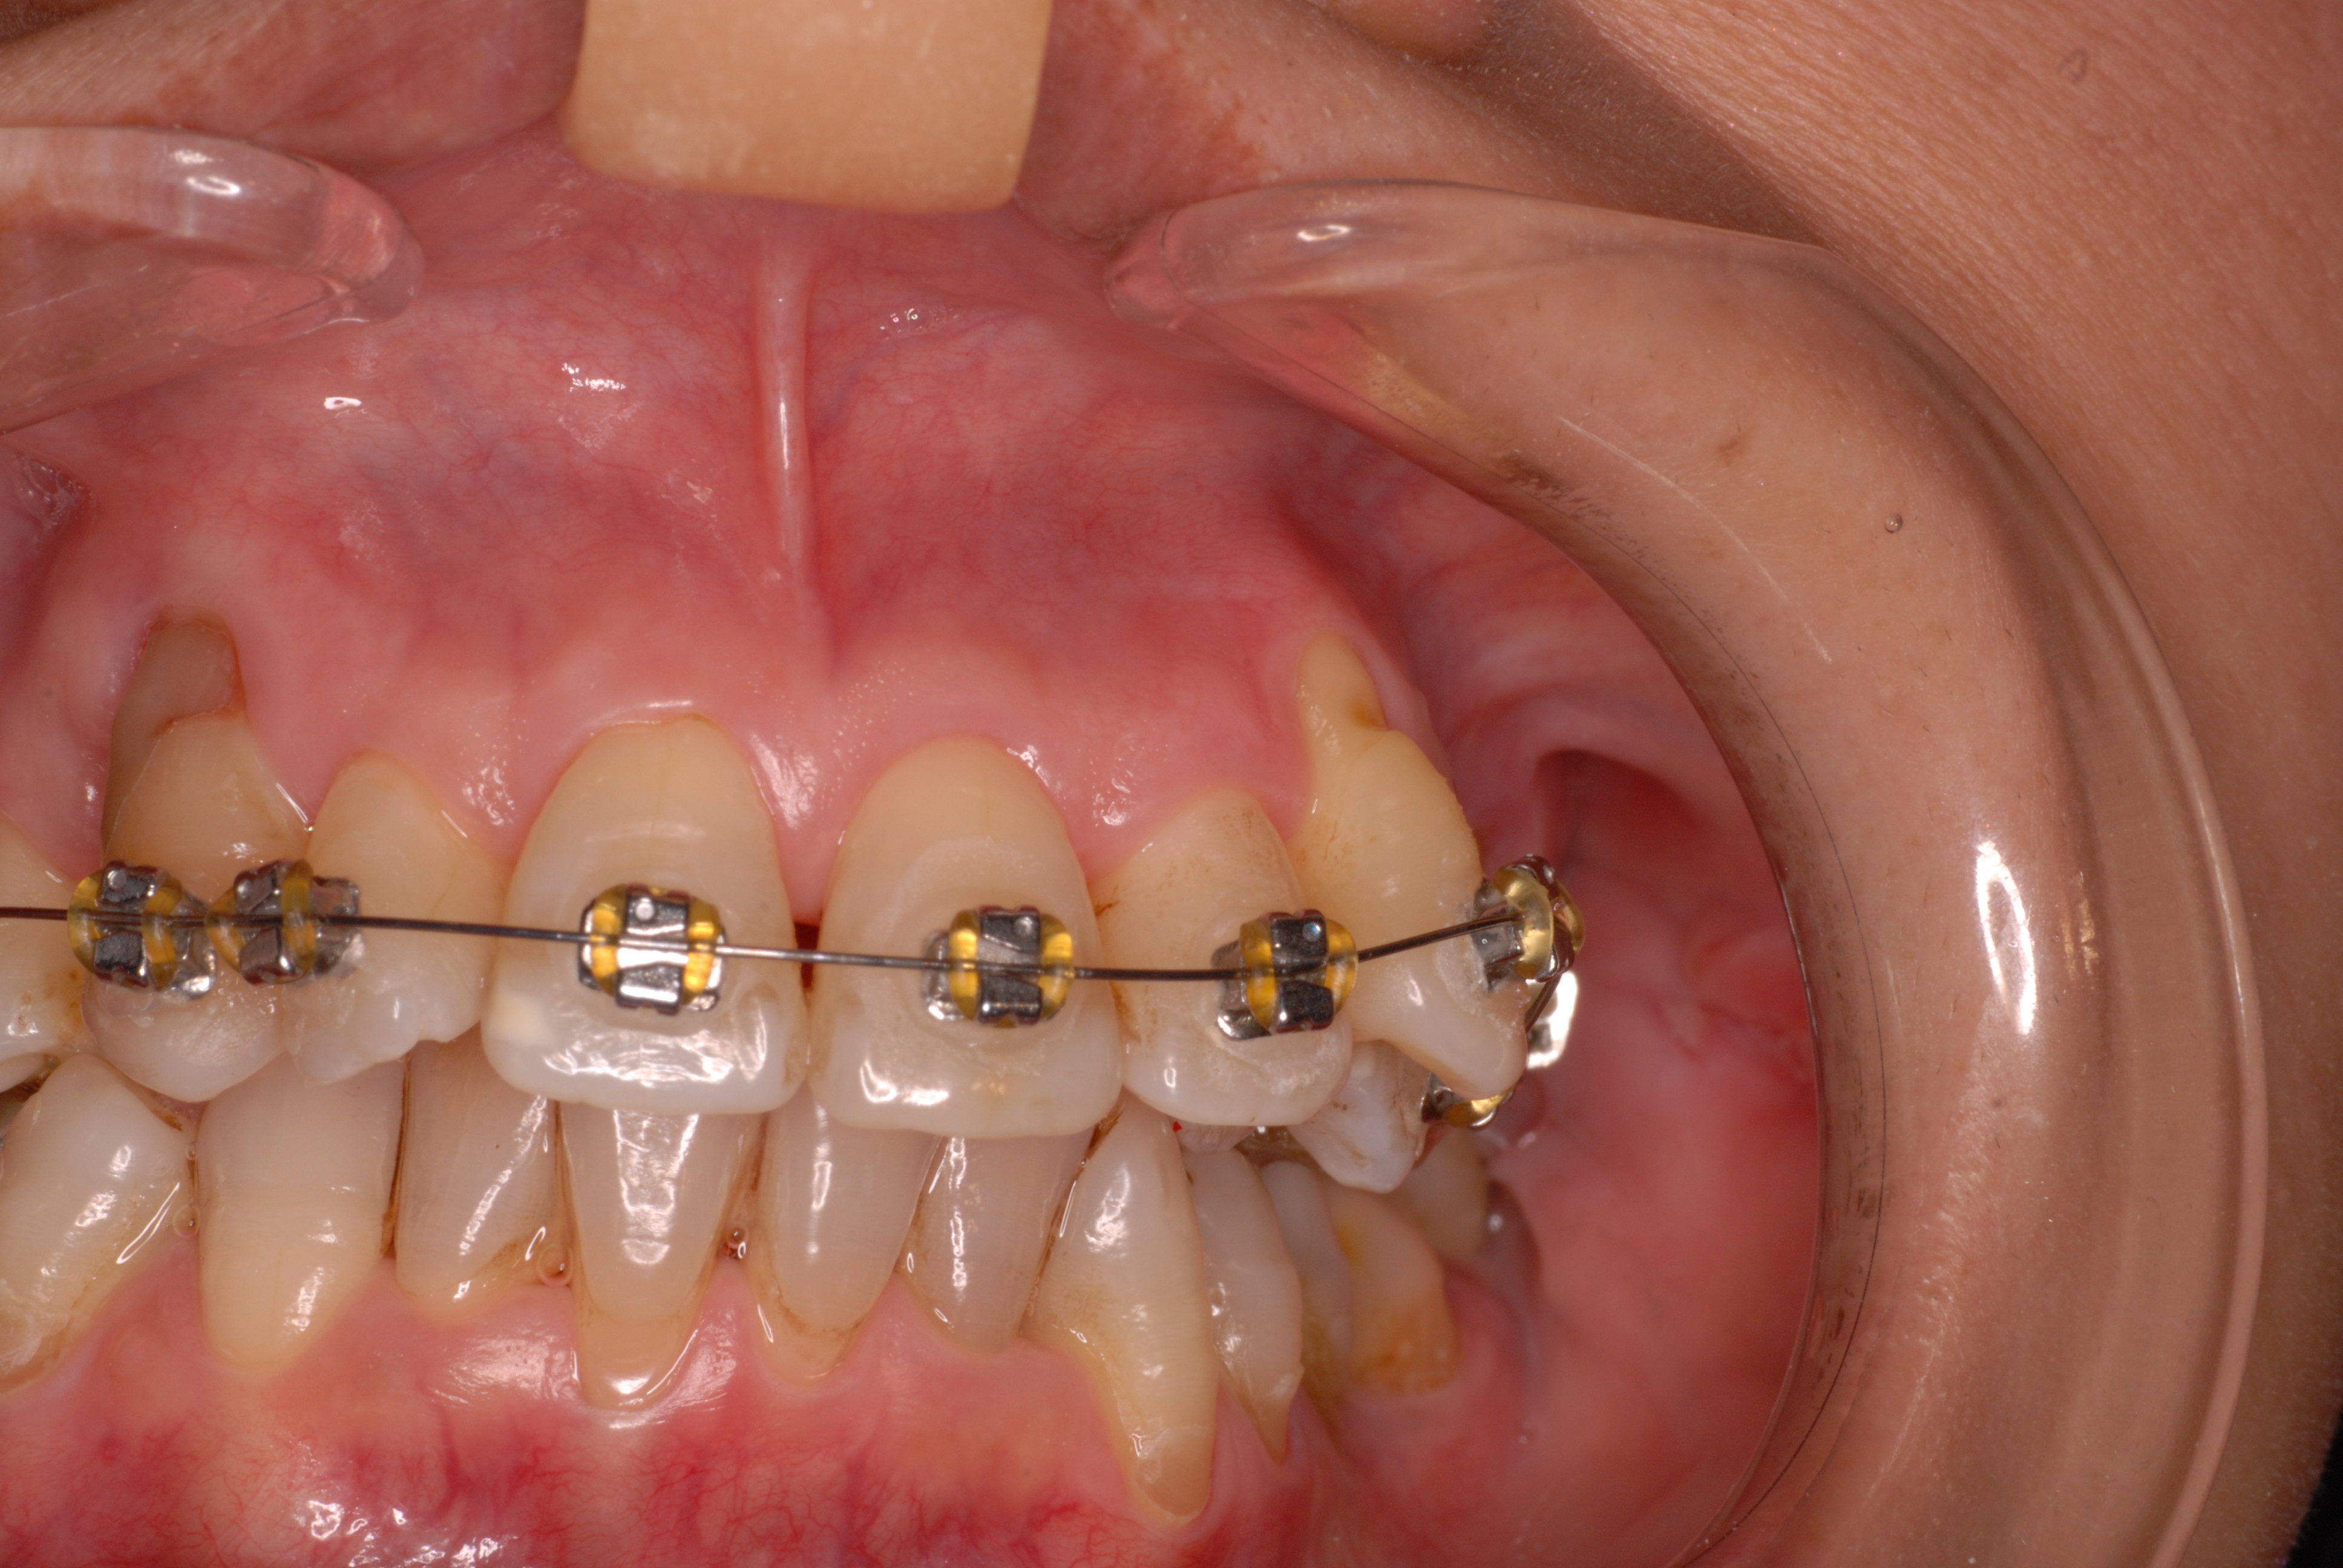

写真左の歯のうち過剰歯と糸きり歯の隣を抜きました。

矯正治療一ヶ月後です。歯並びのガタガタはすぐよくなっています。

矯正は簡単なのですが、虫歯や歯周病にならないように、又かみ合わせや関節、筋肉に問題を起こさないように矯正するのは難しいのです。